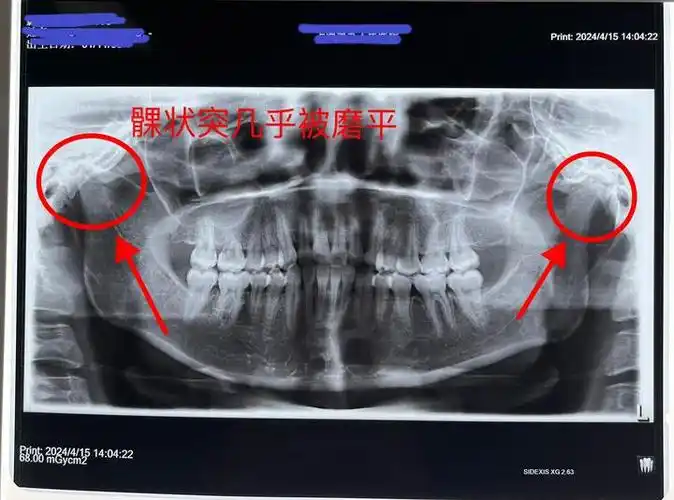

颞下颌关节保守治疗能让髁状突长回去吗?